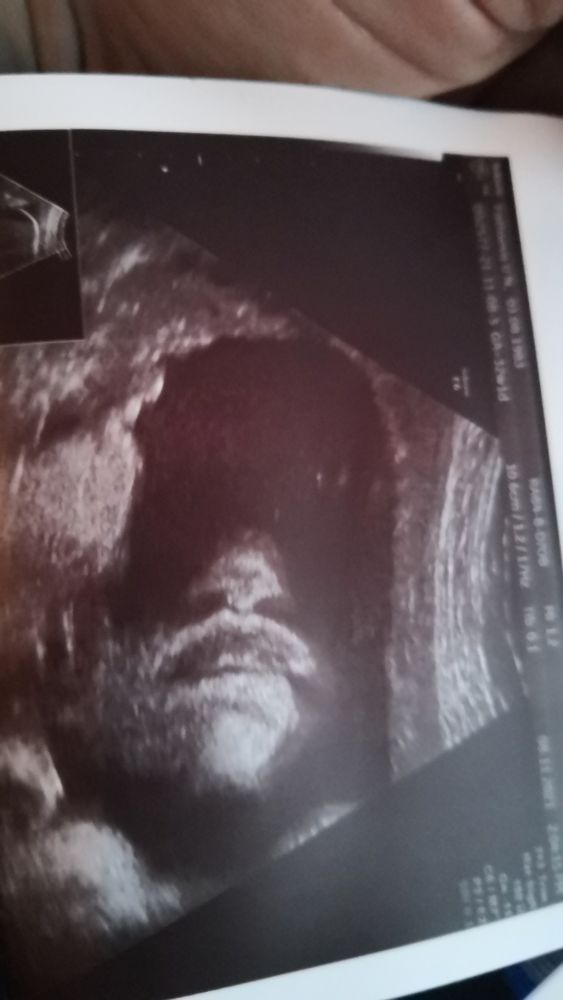

Ух, можно чуть расслабить булки! Пройден наш 3ий скриниг и фиг знает какое по счету УЗИ🤪

Давненько уже не было такого, что практически все у нас хорошо🔥Кровотоки в норме, органы все развиты правильно. Как обычно отстают животик и ножки, на нижней границе нормы. Вроде даже мизинчики увидели, правда коротенькое, но все фаланги есть и носик на месте. Теперь нужно как-то собраться с мыслями и договориться с выбранным врачем на роды. Совсем не умею этого делать🙈😜